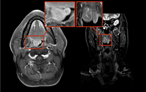

A rare presentation of a paediatric patient with acute otomastoiditis media caused by mycobacterium tuberculosis resulting in intracranial complications

N Jayakody and others

Journal of Surgical Case Reports, Volume 2019, Issue 4, April 2019, rjz093, https://doi.org/10.1093/jscr/rjz093